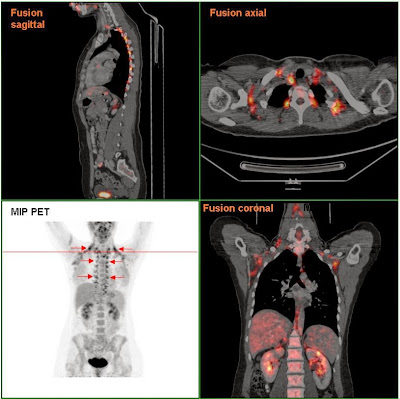

Этим открытием мы обязаны появлению нового метода визуализации активного метаболизма в ткани – позитронно-эмиссионной томографии, объединенной с компьютерной томографией (fused PET-CT), показавшей, что взрослый человек имеет около 20-30 граммов (так мало) функционального бурого жира, преимущественно в надключичной области.

PET-CT регистрирует метаболическую активность ткани, и на правом рисунке мы видим, как нарастает активность бурого жира в ответ на холодовой стресс у взрослого человека.

«Мы выдали 24 молодым людям определённую дозу радиоактивной глюкозы, – рассказывает физиолог Ваутер ван Маркен Лихтенбелт . – Это было сделано для того, чтобы потом иметь возможность обнаружить активную бурую жировую ткань с помощью специальной аппаратуры». Затем участников исследования привели в комнату, температура в которой не превышала 16 °С. PET- и CT-сканирование показало, что под кожей шеи, груди и живота 23 человек присутствует «полезная» жировая ткань, которая работала, согревая людей в холодном помещении.

«Мы очень удивились, когда обнаружили её так много и у такого большого количества людей!» — восклицает ван Маркен Лихтенбелт. Когда же троих участников обследовали при комнатной температуре, то не нашли никаких следов бурого жира. Это не значит, что ткань исчезла, просто она перестала активно работать, считают эксперты.